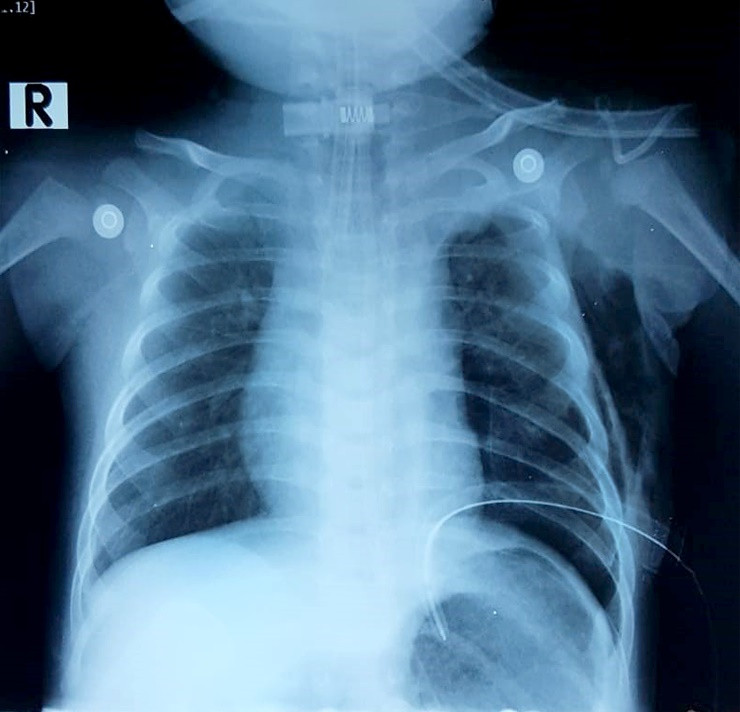

Ngay khi tiếp nhận bệnh nhân, bác sĩ chỉ định chụp X quang, xét nghiệm. Kết quả cho thấy bé bị tràn dịch màng phổi bên trái, gây chèn ép nhu mô phổi. Bệnh nhi bị rò dịch dưỡng trấp nghi do rò từ ống ngực vào khoang màng phổi.

| Hình ành chụp X quang cho thấy bệnh nhi bị rò dịch dưỡng trấp nghi do rò từ ống ngực vào khoang màng phổi. Ảnh: BVCC |